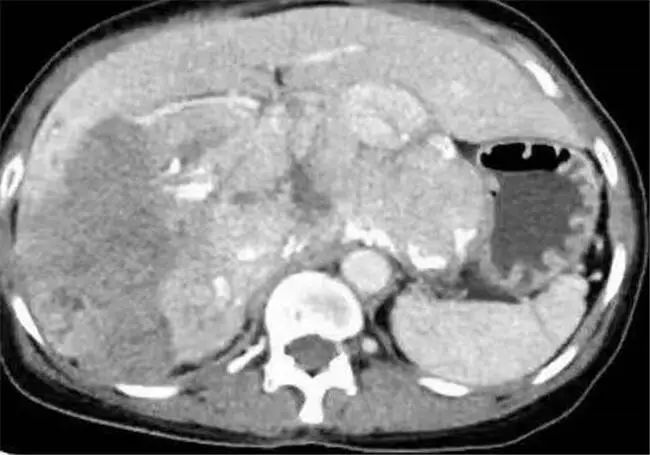

家人送医后CT检查显示:中、上腹巨大不均质肿物,填塞肝门,贴压胆囊、胰腺、右肾、门静脉、下腔静脉,考虑恶性。病人和家属立刻感到紧张和无助,虽在各大医院辗转求诊,均表示治疗意义不大。但病人和家属均不想放弃,怀着最后一丝希望,来到云南省第三人民医院肝胆胰外科就诊。

患者入院后,经过仔细检查后发现这名患者中上腹巨大不均质肿物已经填塞肝门,与肝实质分界不清,贴压胆囊、胰腺、右肾、门静脉、下腔静脉,手术操作的空间非常小。其次,患者身体基础条件十分不好,长期高血压,心肺功能极差,肝功能下降,手术难度极大。

6月5日8时,手术正式开始。江行带领专家手术组历时6个小时,实施了切除、重建、修补过程,最终,顺利完成巨大肿瘤切除+右半肝、全尾状叶切除术+胆囊切除术,成功从患者体内取出长约27厘米,重达4.21千克的肿瘤。